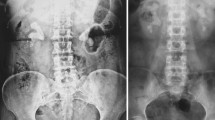

There has been continuing controversy regarding multiple tracts in a percutaneous nephrolithotomy (PCNL) session that may bring more complications, especially severe bleeding need for transfusion, even nephrectomy. Little tracts may bring less trauma to renal parenchyma than standard PCNL tracts. We carried minimally invasive PCNL (MPCNL) in treating staghorn calculi with multiple 16Fr percutaneous tracts in a single session, in an attempt to get high stone free with little trauma, and compared the morbidity of standard PCNL procedures in a prospective trial. A total of 54 consecutive patients with staghorn calculi were prospectively randomized for MPCNL (29) and PCNL (25). The size and location of stone, operative parameters, number of tracts, stone-free rate, operating time, hospital stay and complications were analyzed. In MPCNL group, a total of 67 percutaneous tracts were established in 29 renal units, while 28 tracts in 25 renal units in PCNL group. Compared to PCNL, MPCNL was associated with higher clearance rate (89.7 vs. 68%, p = 0.049), less chance need for adjunctive procedure of SWL or second-look PCNL (24.1 vs. 60%, p = 0.007), while a similar complication rate (37.9 vs. 52%, p = 0.300). In conclusion, with the development of instruments and increased experience, judiciously made multiple percutaneous tracts in a single session of MPCNL for treating staghorn calculi were safe, feasible and efficient with an acceptable morbidity.